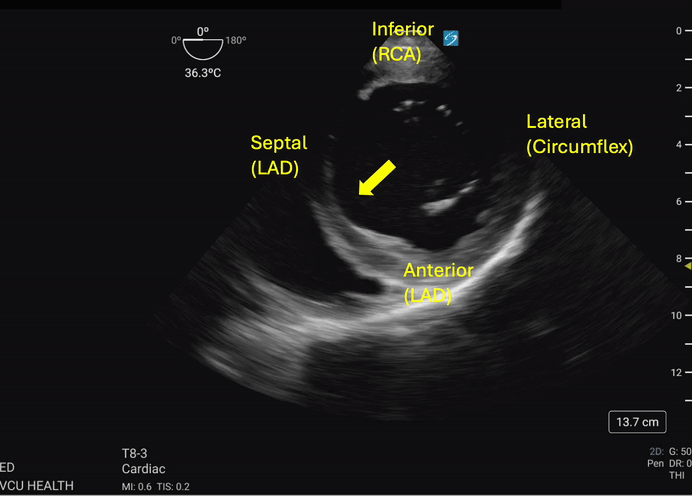

Hypokinesis or akinesis of the left ventricular myocardium segments can indicate tissue ischemia or infarction in specific vascular territories (Figures 3a and 3b). The RCA supplies the myocardium of the inferior wall of the left ventricle. On TEE, the inferior wall is located closest to the probe footprint, since the probe is coming from the stomach located inferior to the heart. The LAD supplies the myocardium of the anterior and septal portions of the left ventricle. The circumflex artery supplies the lateral portion of the left ventricular myocardium and will be shown on the rightward aspect of the ultrasound image.4

Figure 3b. The septal wall exhibits focal akinesis (arrow) in addition to global hypokinesis which may suggest an acute LAD lesion in the right clinical context. Image courtesy of Lindsay Taylor, MD.